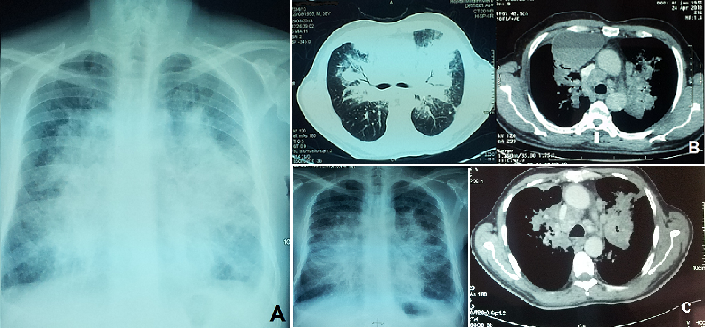

Nous rapportons l'observation d'un patient âgé de 58 ans, sans antécédent particulier; se plaignant 1 mois avant son hospitalisation d'un syndrome bronchique, des hémoptysies minimes et une dyspnée d'aggravation progressive devenant une dyspnée au repos évoluant dans un contexte d'apyrexie et d'amaigrissement non chiffré. L'examen clinique trouvait un patient dyspnéique à 28 c/min avec des râles ronflants perçus à l'auscultation pleuro-pulmonaire. La radiographie thoracique montrait un syndrome alvéolaire para-hilaire bilatéral réalisant un aspect en Aile de Papillon (A) faisant évoquer un oedème aigue des poumons. Le scanner thoracique découvrait une collection para-médiastinale droite mesurant 123x110x86 mm à paroi fine et refoulant le médiastin et le parenchyme pulmonaire; avec infiltration tissulaire péri-hilaire et péri-bronchique avec contours externes nets réalisant un aspect en aile de papillon; présence d'adénopathies médiastinales et sous diaphragmatiques (B). La bronchoscopie montrait des éperons épaissis plus marqué au niveau de la lobaire supérieure droite; les orifices rétrécis. Des biopsies bronchiques sur les zones pathologiques ont été faites dont l'étude anatomopathologique et immunohistochimique a conclue à un adénocarcinome moyennement différencie et infiltrant d'origine pulmonaire. Le patient a reçu 6 cycles de chimiothérapie antimitotique. L'évolution est marquée par une stabilité clinique et régression partielle des anomalies radiologiques avec nettoyage de la collection médiastinale (C) sur un recul de 15 mois. L'adénocarcinome pulmonaire primitif représente actuellement le type histologique le plus fréquent du cancer du poumon; de topographie habituellement périphérique mais, d'autres aspects peuvent néanmoins exister.